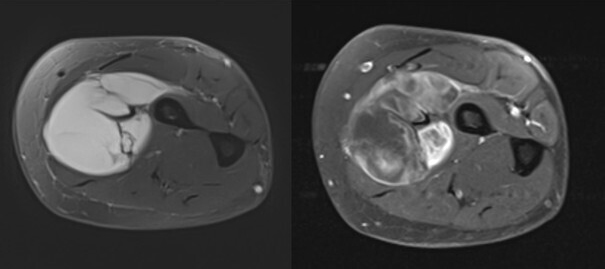

Concernant les tumeurs des membres, on distingue premièrement les lésions graisseuses, qui sont majoritairement représentées par les lipomes bénins. Ces lésions ne nécessitent pas d’examen complémentaire si elles ont une taille inférieure à 5 cm en situation profonde (intramusculaire) ou 10 cm en situation superficielle (dans la graisse sous-cutanée au-dessus des fascias musculaires). Au-dessus de cette limite de taille, il est recommandé de réaliser une imagerie par résonance magnétique (IRM), à la recherche de signes d’atypie. L’objectif est de reconnaître les potentiels liposarcomes et les tumeurs graisseuses atypiques (liposarcomes bien différenciés). Dans les autres cas de figure, c’est-à-dire pour les tumeurs non graisseuses, ou les pseudotumeurs, ou pour les tumeurs osseuses qui ne sont pas aisément caractérisables, le recours à l’IRM doit être systématique (figure). Certaines lésions restent d’orientation difficile, et il est de rigueur de prôner la prudence en envoyant le patient dans un centre expert et/ou en organisant une surveillance radioclinique. Pour inciter à la prudence, on évoque volontiers les cas souvent décrits des lésions sarcomateuses prises par erreur pour des hématomes et les radiographies normales des sarcomes osseux de l’enfant au stade précoce. Une évolution clinique péjorative doit être systématiquement accompagnée d’une investigation radiologique par IRM.